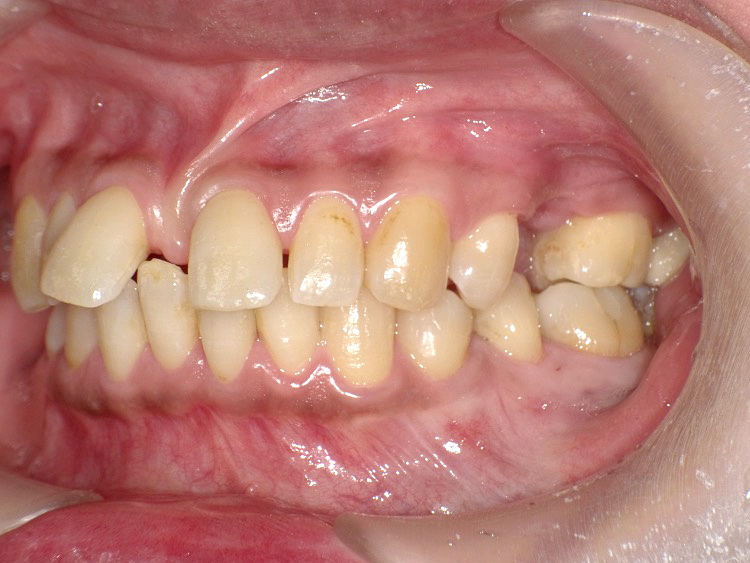

症例4

Before

After

| 主訴 | 上下前歯のがたつき |

|---|---|

| 年齢 | --- |

| 治療 期間 |

約9ヶ月 |

| 治療 内容 |

インビザラインiGoで上下顎の治療。 |

| 治療費 | ¥550,000(税込)/調整料含む |

| 治療のリスク | 矯正終了後は、リテーナーを指示通りに使用し、歯の後戻りを防ぐ必要があります。 |